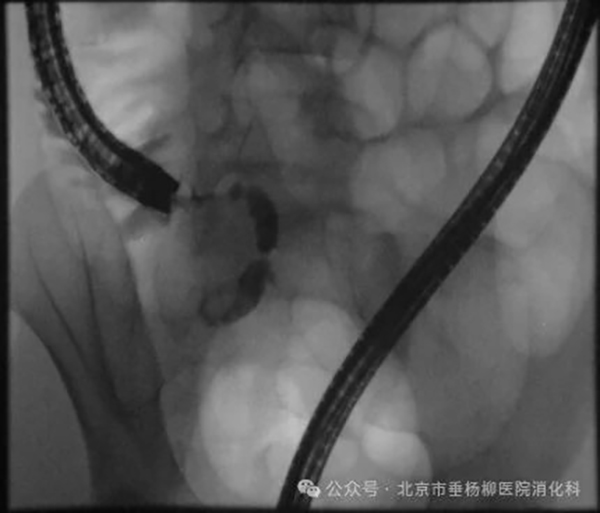

【垂医科普】消化内科:不明原因胸痛、吞…

【垂医科普】消化内科:阑尾炎不必切阑尾…